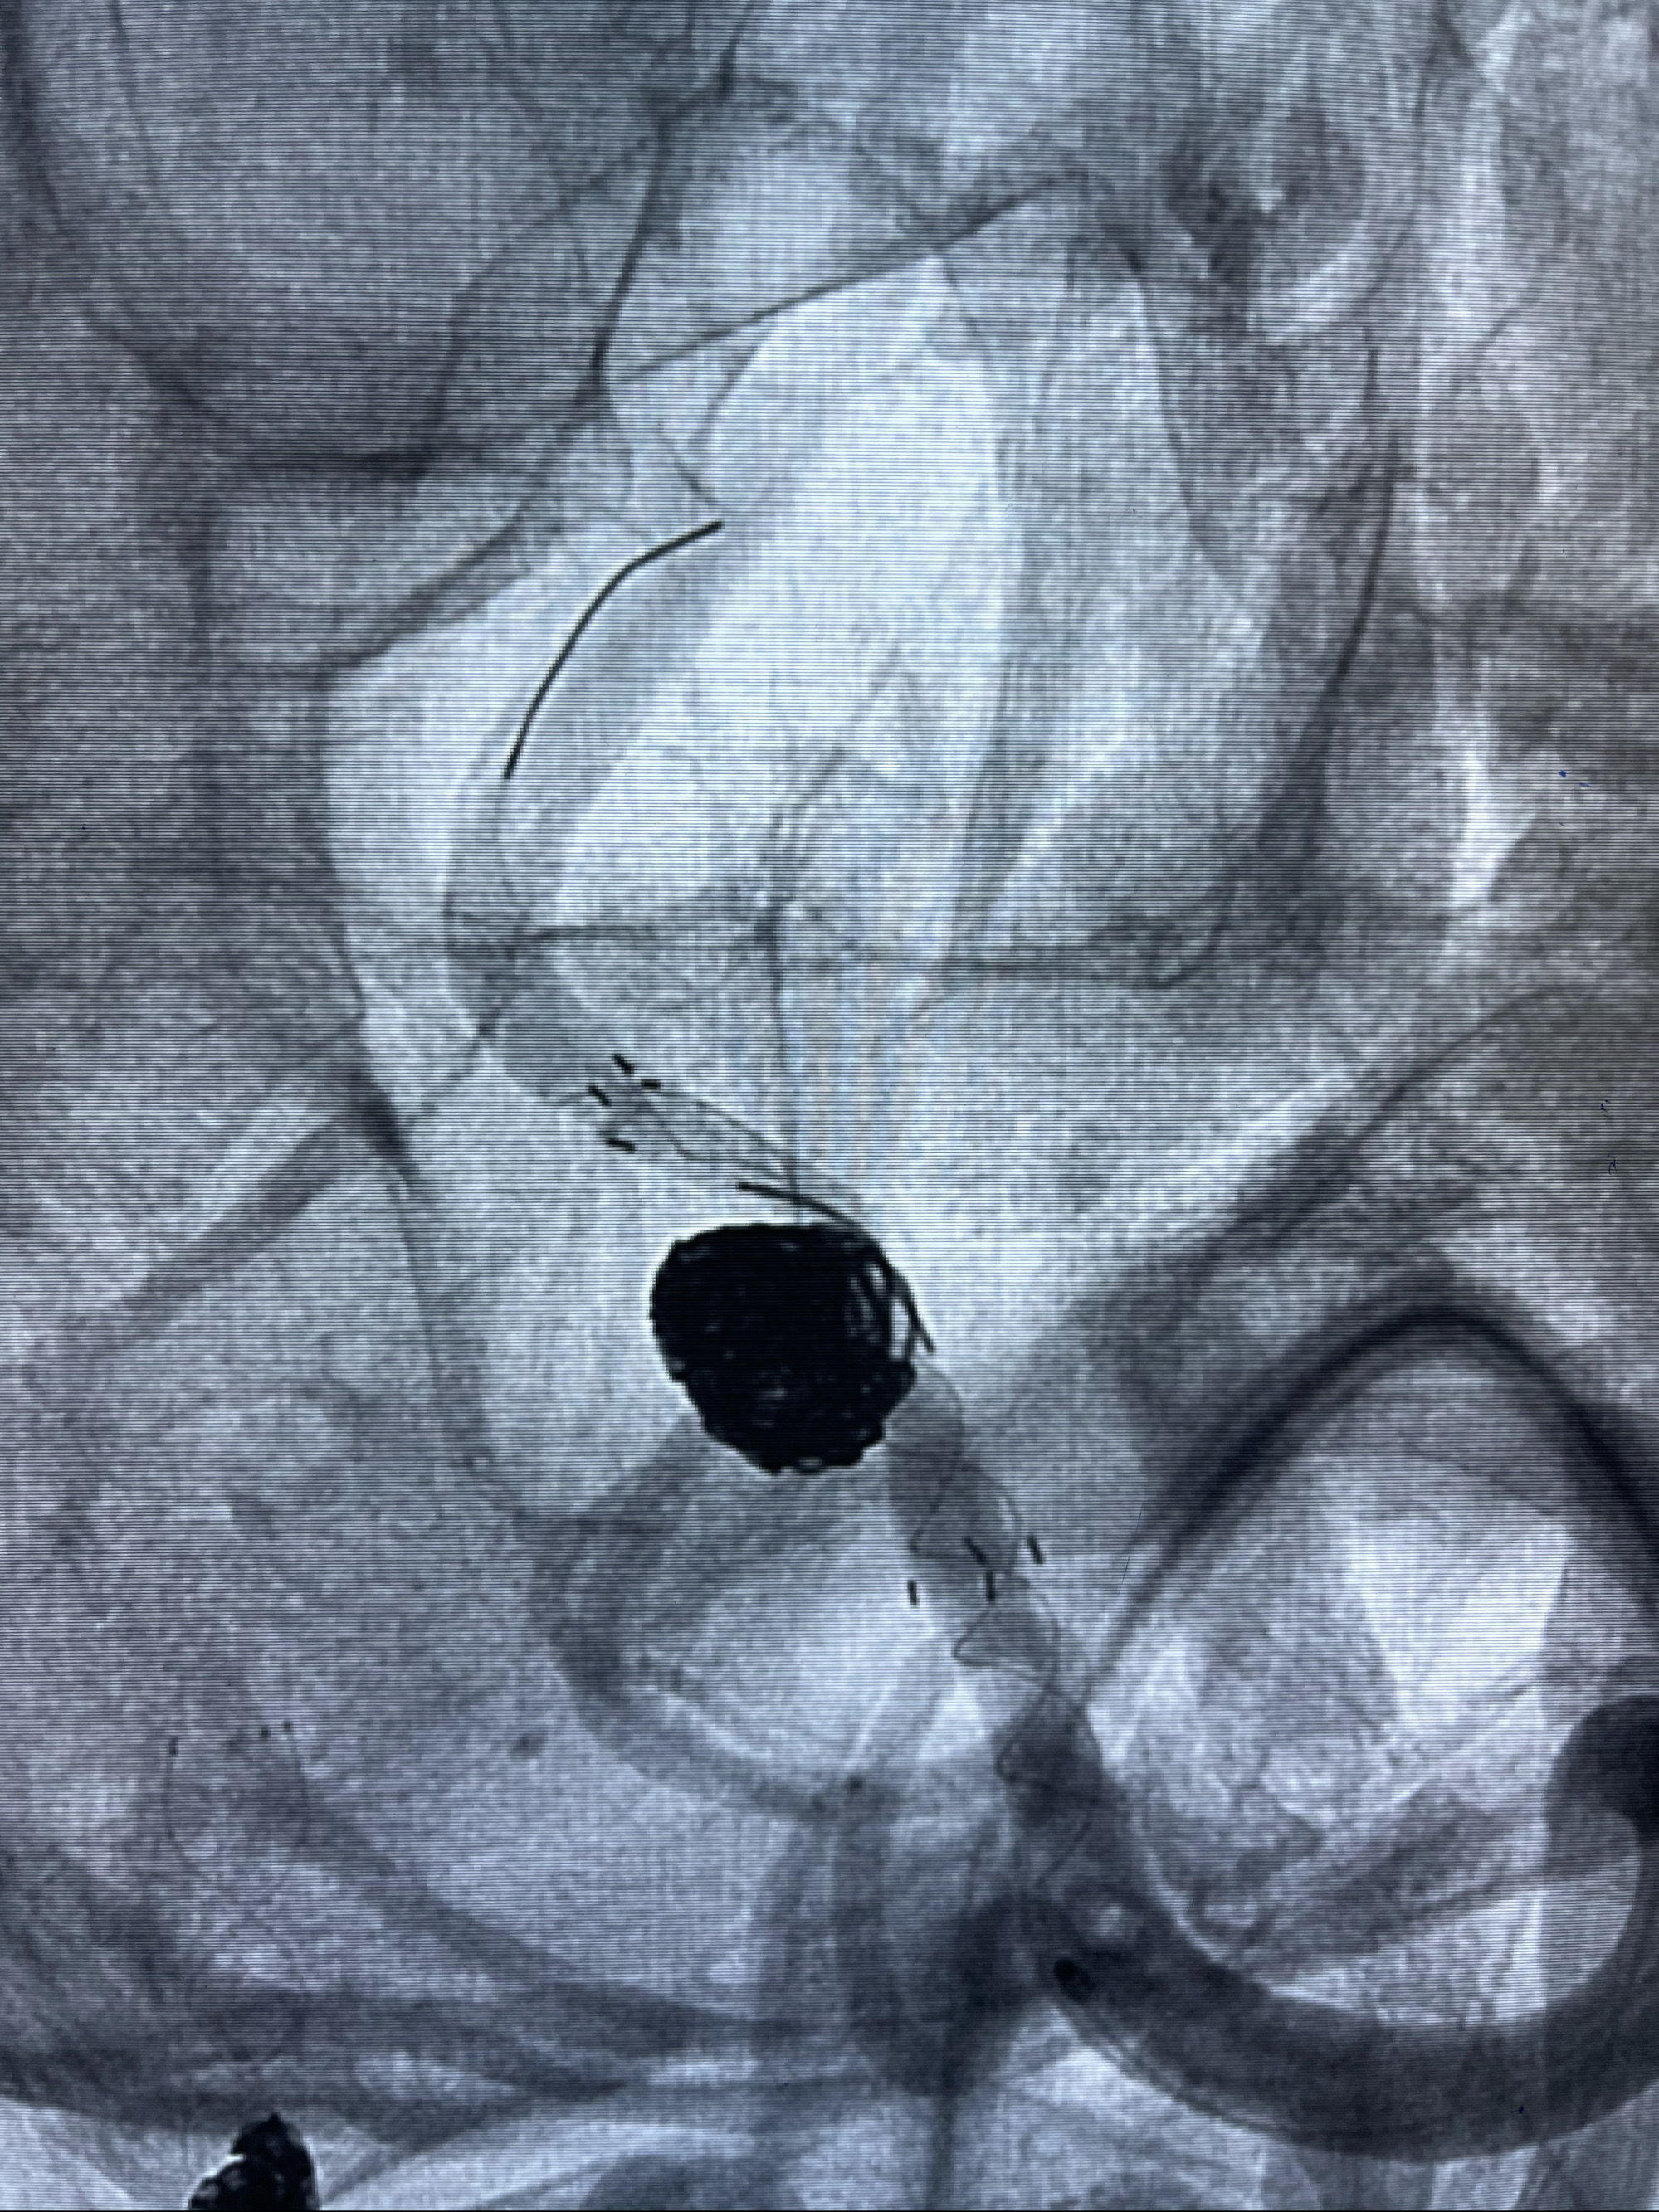

工作角度造影

8mm-40cm微弹簧圈成篮

即刻造影